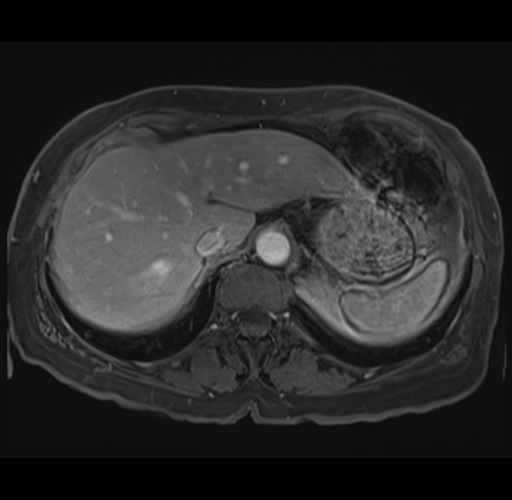

MRI T1